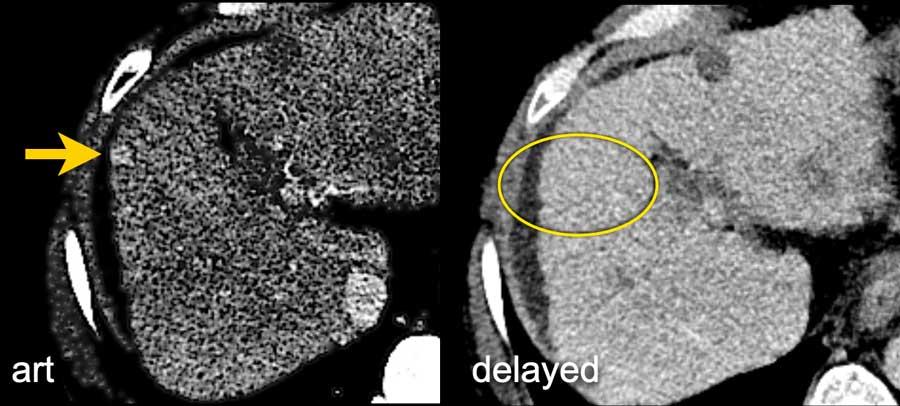

Thì động mạch muộn

Thì này tương ứng với thì động mạch gan, trong đó động mạch gan và các nhánh ngấm thuốc hoàn toàn trong khi các tĩnh mạch gan chưa ngấm thuốc.

HCC thường ngấm thuốc mạnh hơn trong thì động mạch muộn, biểu hiện ngấm thuốc sớm của tĩnh mạch cửa, do đó được ưu tiên hơn so với thì động mạch sớm — khi tĩnh mạch cửa chưa ngấm thuốc và HCC ngấm thuốc kém.

Lưu ý hình ảnh ngấm thuốc kém của nhu mô gan và tĩnh mạch cửa (mũi tên trắng) trong thì động mạch sớm, và ngấm thuốc tốt của cả động mạch gan (mũi tên trắng) lẫn tĩnh mạch cửa (mũi tên xanh) trong thì động mạch muộn.